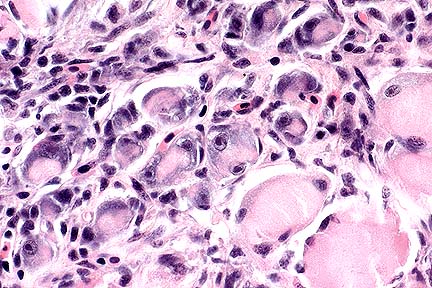

Numerous PAS-positive neuronal and glial inclusions in the cerebellum of a Maine Coon cat with tremors and seizure-like activity. (PAS, 100X, 65K)

Higher magnification of the field above, showing cytoplasmic inclusions within several Purkinje cells, as well as inclusions in unidentified cells in the molecular layer. (HE, 400X, 48K)

Contributor's Diagnosis and Comments: Cytoplasmic polyglucosan inclusions (Lafora bodies) within neuronal perikarya and processes, most numerous in Purkinje cells.

In sections of brain, there are few to many basophilic to amphophilic inclusions that occur within the cytoplasm of nerve cell bodies, neuronal processes, and scattered in the neuropil. These inclusions are usually round, range in size from 2 to 10 um diameter, and occasionally have a pale center or a thin, striated halo. These Lafora-like bodies are most numerous in the cerebellar molecular layers and within Purkinje cells, but are observed in all examined sections of brain.

Lafora bodies consist of complex polymers of glycoprotein, sometimes designated "polyglucosan bodies", and can occur within neuronal cell bodies or processes of the brain, spinal cord, or retinal ganglia. The round to globular basophilic cytoplasmic inclusions stain positively with PAS, alcian blue, and methenamine silver. In domestic animals, Lafora bodies have been observed most commonly in aging (at least 8 years of age) dogs and cats without apparent neurologic disease, but have also been described as incidental changes in some young animals. Lafora bodies have also been associated with a severe form of progressive myoclonus epilepsy in humans (juveniles) and dogs (young adult to middle-age), reflecting widespread intra-neuronal storage of these polyglucosans ("Lafora disease" or "neuronal glycoproteinosis"). The absence of other lesions to account for the observed neurologic signs incriminates the Lafora bodies as playing a role in the reported neurologic signs in this cat. In dogs with associated neurologic disease, the deposits are most commonly observed in Purkinje cells, similar to the distribution noted in this cat. In children with Lafora disease, other sites of polyglucosan deposition include skin and liver, and biopsies of these tissues have been used to help establish the diagnosis. Lafora bodies were not found in tissues from other than the CNS in this cat.

AFIP Diagnosis: Cerebellum, molecular and Purkinje cell layers: Polyglucosan bodies (Lafora bodies), neuronal and extracellular, diffuse, numerous, Maine-Coon, feline.

Conference Note: This case was also reviewed by AFIP's Department of Neuropathology. Lafora bodies are complex glycoprotein neuronal inclusions that can occur in the perikaryon, dendrites, or axons. They are PAS-positive and stain with alcian blue and methenamine silver. They can be found anywhere in the neuraxis and in retinal ganglion cells. Polyglucosan bodies have been associated with neurologic disease in humans, cats, dogs (Beagles, Basset Hounds, and Poodles), and a cockatiel. Lafora's disease in humans is a rare familial neurologic disorder of children. The disease is progressive and manifested by myoclonus. The characteristic histologic feature in the human disease is intraneuronal polyglucosan bodies, which occur predominantly in the substantia nigra and dentate nucleus. In dogs with neurologic disease attributed to the accumulation of intraneuronal polyglucosan bodies, the bodies are found predominantly within Purkinje cells and in thalamic neurons. In animals, Lafora bodies are frequently seen in the absence of neurologic disease. In these cases, the Lafora bodies can be found in any area of the brain and in the spinal cord.